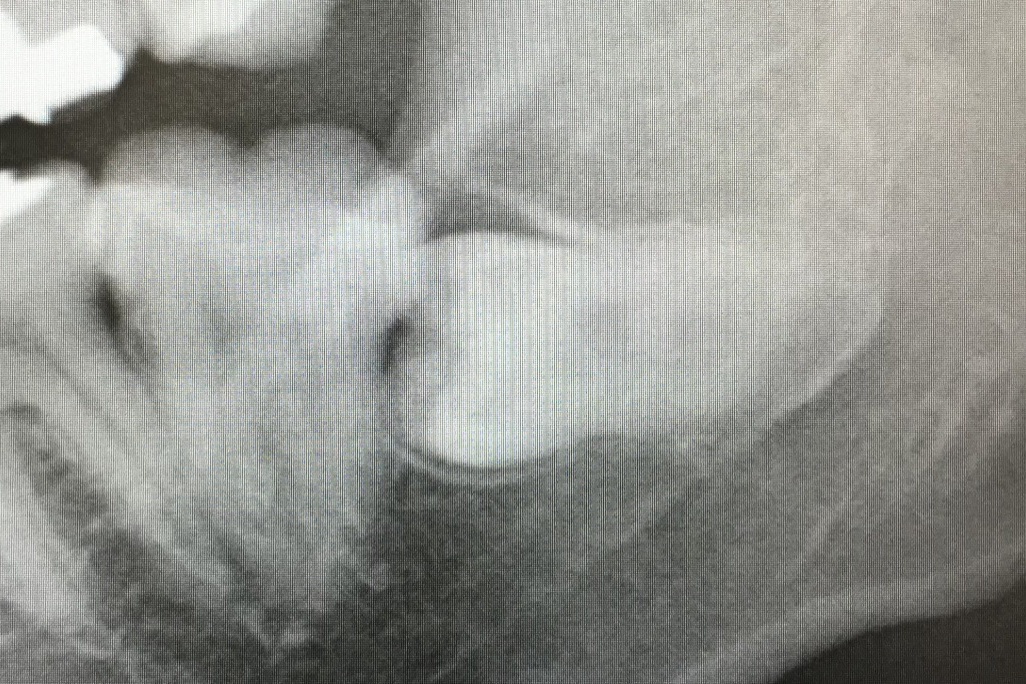

☆☆☆☆

レントゲンを見た瞬間,冷や汗がでます.こ,これは難しいぞぉ.30分くらい頑張ってください.もちろん静脈内鎮静が保険適応になりますので,怖い方はご相談くださいね.これは初診日抜歯,勘弁してください.